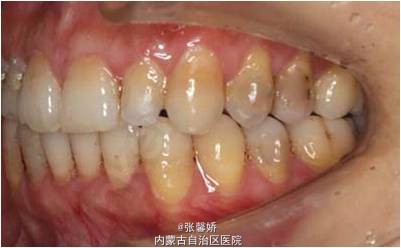

随访 讨论

一年后随访,患者咬合关系仍稳定,尖窝锁结良好。 隐形矫治适应证的选择很重要,适合中低难度的成人病例,患者的配合和依从性要求较高。 此患者术前全景片可见多个充填物,为龋易感患者,而且牙周也不是很好,隐形矫治没有拖槽更利于患者口腔卫生的维护,防止龋病的发生和牙周病的加重。